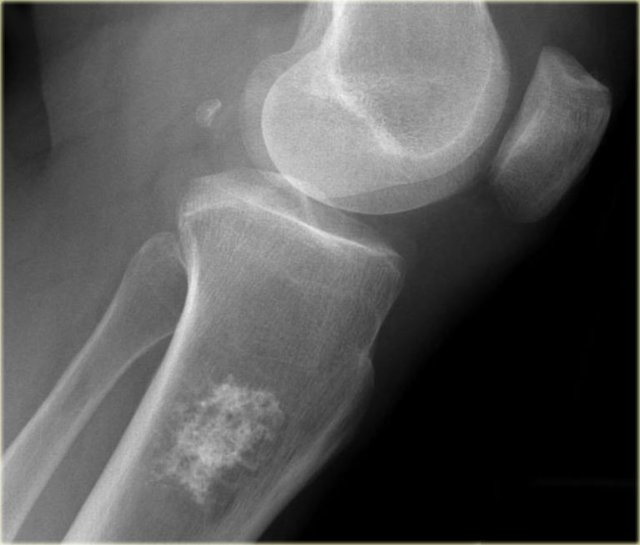

The image shows a calcified lesion in the proximal tibia without suspicious features.

This could very well be an enchondroma.

There were other features that favored the diagnosis of a low-grade chondrosarcoma like a positive bone scan and endosteal scalloping of the cortical bone on an MRI (not shown).

A chondrosarcoma was diagnosed at biopsy.